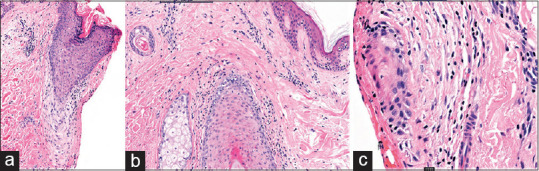

Immune checkpoint inhibitors (ICIs) have revolutionized cancer therapies. Their mechanism promotes a cytotoxic T-cell activation against the tumor cells, but as a consequence, immune-mediated toxicities are increasingly being identified. Cutaneous immune-mediated adverse events (AE) occur in 32% of patients, with possible higher grade AEs seen with anti-programmed cell death protein 1, such as nivolumab. A 67-year-old woman with metastatic melanoma, previously treated for 2 years on dual ICI (ipilimumab and nivolumab), had her treatment interrupted due to grade-3 hepatitis. She was subsequently recommenced on single-agent nivolumab with good response, before discontinuation due to remission. She reported worsening scalp pruritus with associated erythema, scaling, and global hair thinning. On examination, she had significant erythema throughout the scalp with perifollicular scaling and evidence of scarring. She reported severe distress from her symptoms. Her scalp biopsy demonstrated features of scarring alopecia with infundibular and isthmic inflammation and interface change in keeping with lichen planopilaris. Follicular toxicities are rarely reported, possibly due to imprecise AE phenotyping or underreporting. However, growing evidence suggests that patients can develop follicular pigmentary changes and nonscarring alopecia. To our knowledge, this is the first case of scarring alopecia reported with nivolumab. Current treatments for ICI-induced toxicities are limited.